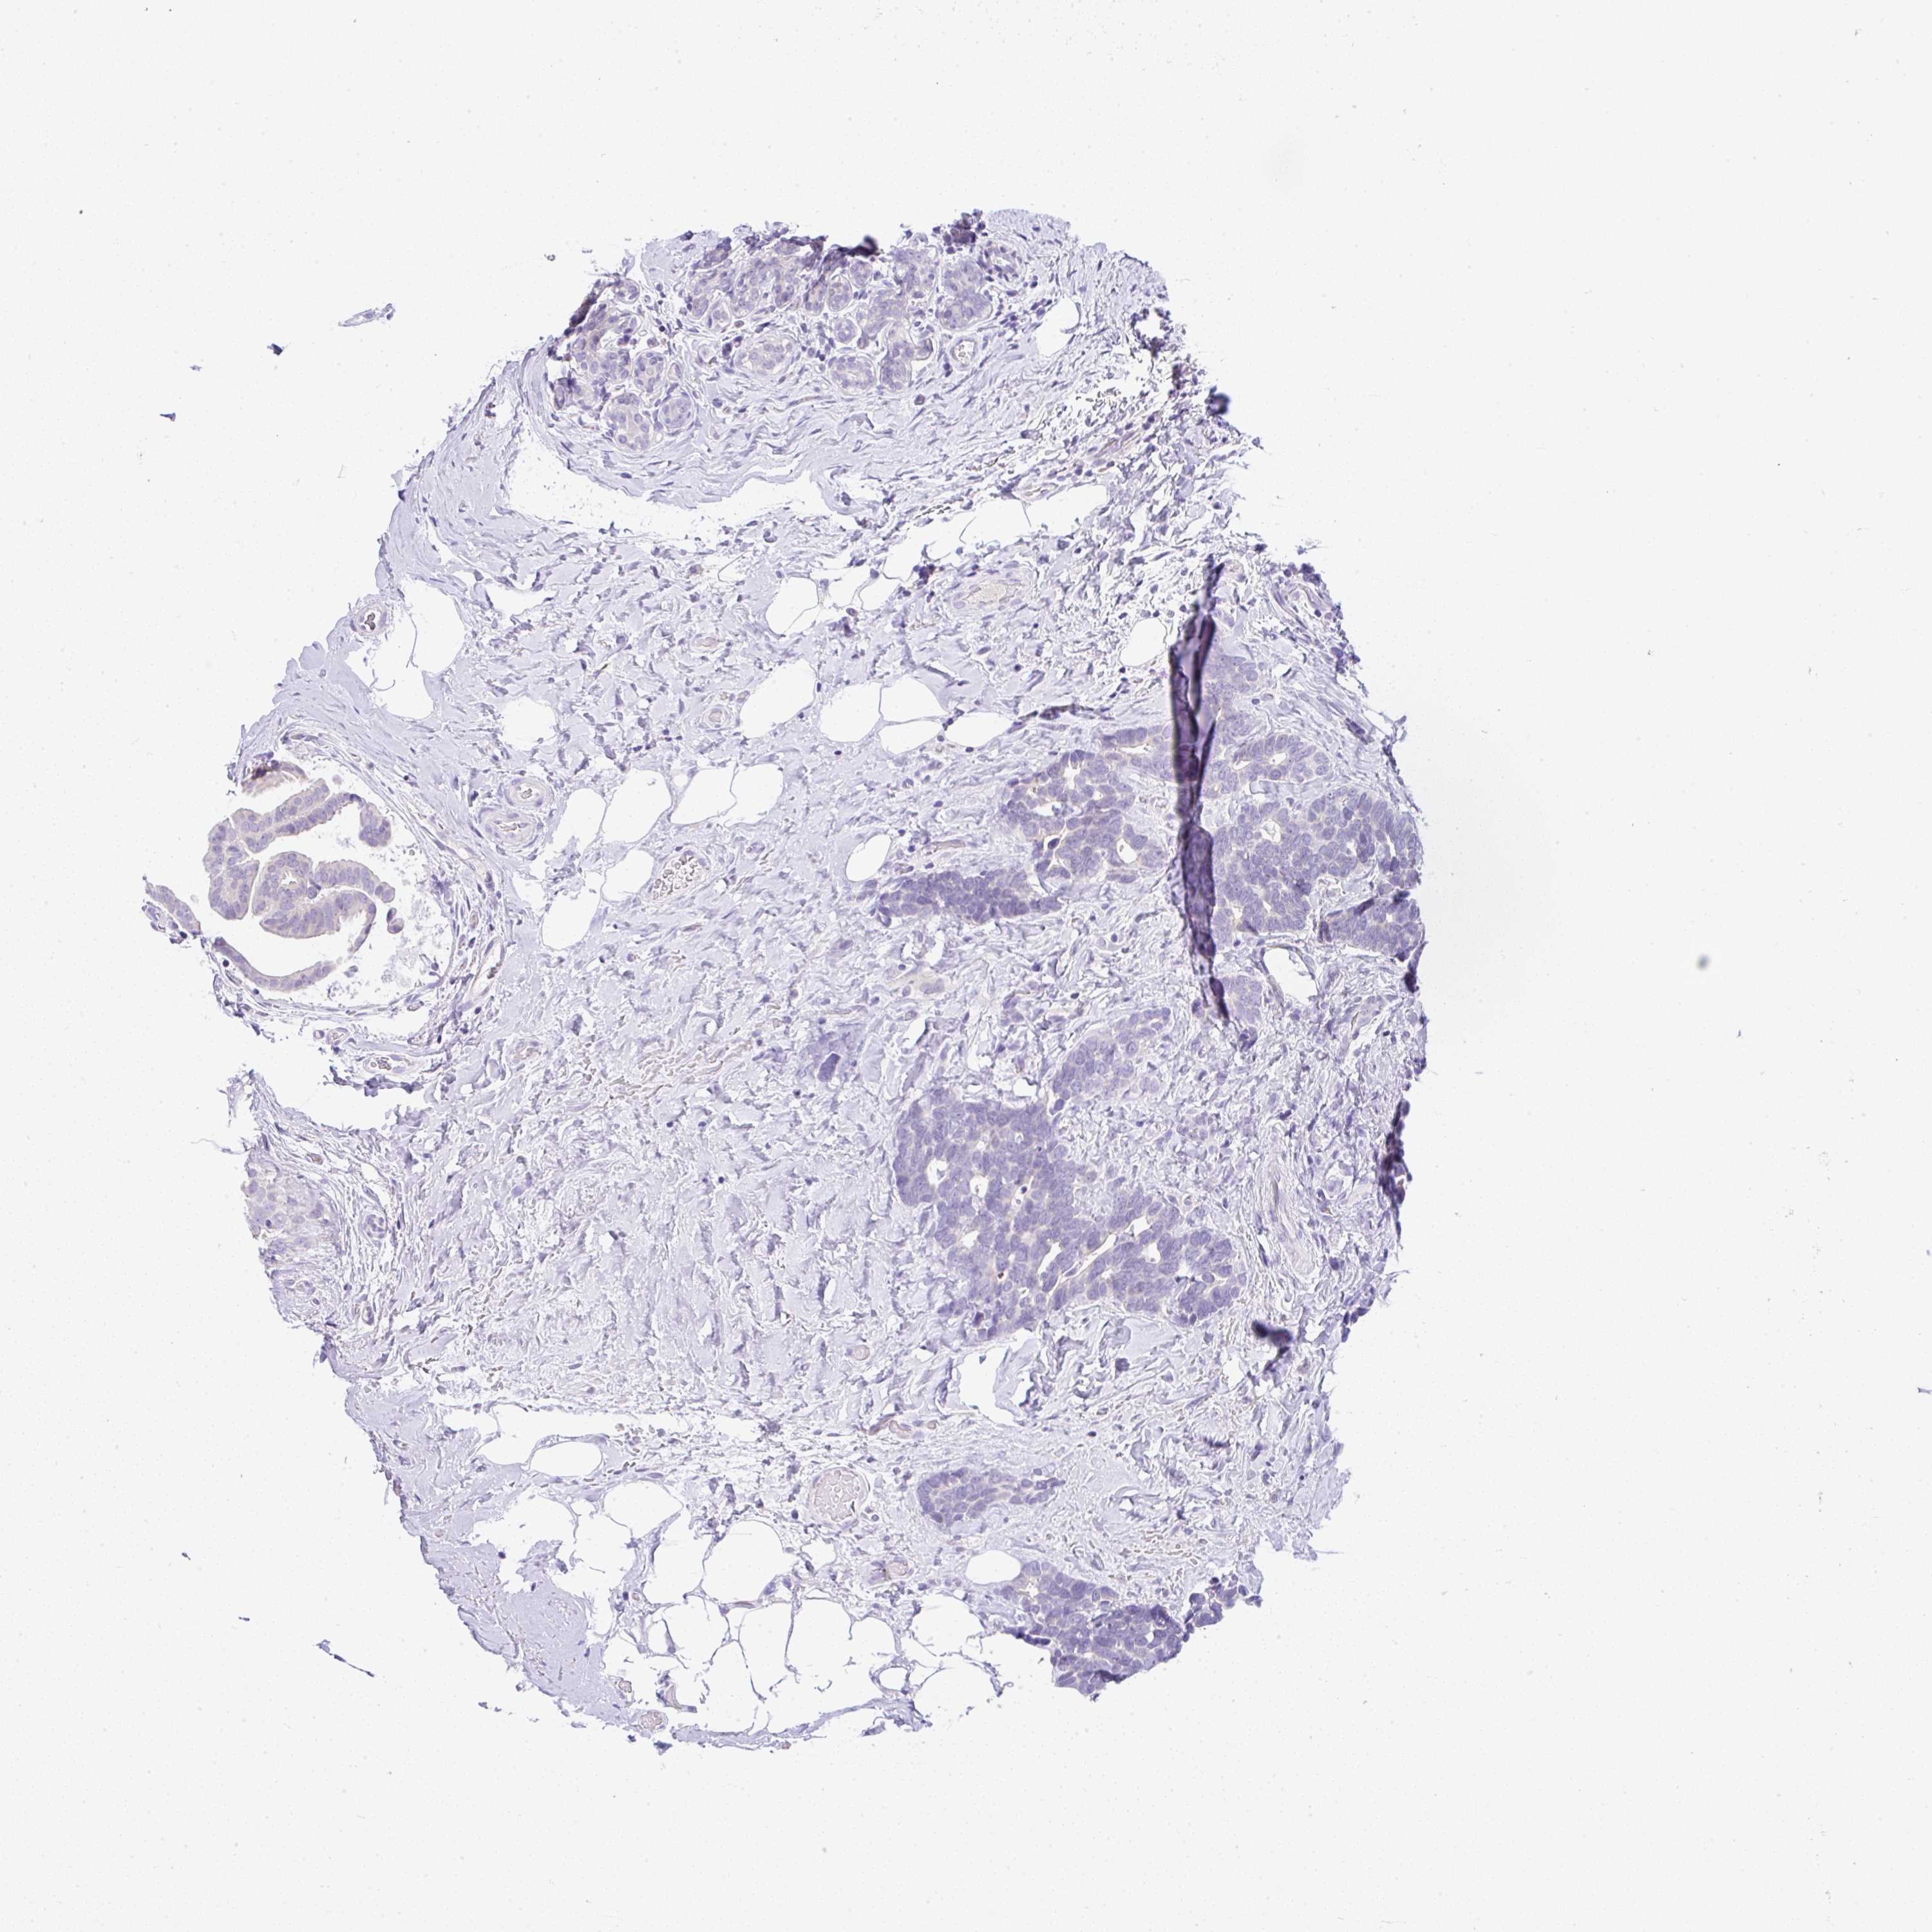

CANCER BREAST CANCER Show tissue menu

BRCA TCGA BRCA VALIDATION PROTEIN EXPRESSION

ANTIBODIES

AND

VALIDATION